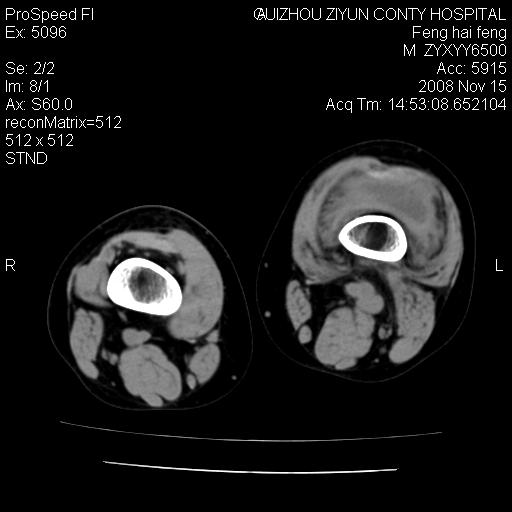

标题: CT16656:M 14Y 左膝关节肿胀一年余。其余病史不详。 [打印本页]

标题: CT16656:M 14Y 左膝关节肿胀一年余。其余病史不详。

考虑左侧髌骨结核;左膝关节滑膜肿胀、增厚,关节囊积液。

左膝滑膜型关节结核可能性大!支持!滑膜型关节结核主要ct表现:关节囊肿胀,积液,关节面见小破坏灶,并见点状死骨!

好大的左腿!考虑左侧髌骨结核,左膝关节滑膜肿胀、增厚,关节囊积液。

左侧髌骨结核;左膝关节滑膜肿胀、增厚,关节囊积液